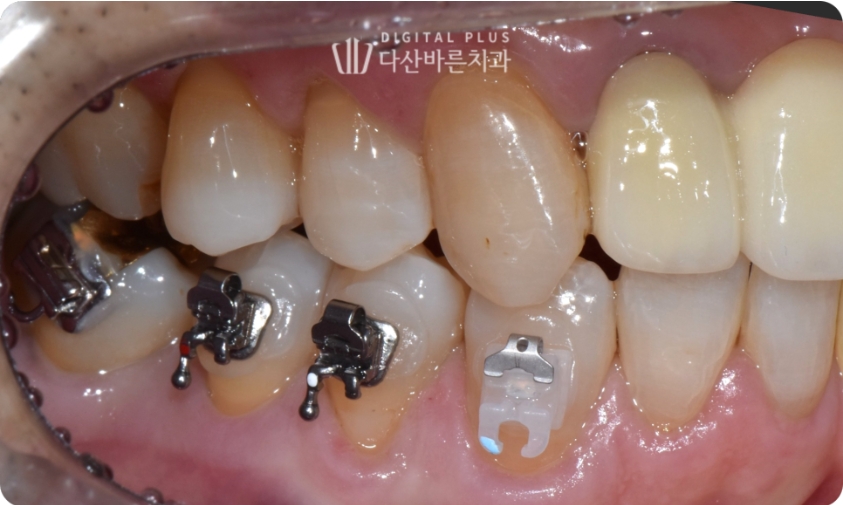

▲ 초진 시 구강 사진. 빠진 치아 자리로 인접치들이 기울어진 모습.

이런 경우 고려할 수 있는 치료 방법은,

- 기울어진 치아 발치 후 임플란트 식립

- 기울어진 치아 교정 후 임플란트 식립

이렇게 크게 두 가지를 고려해 볼 수 있습니다.

원장님 치료 스타일마다 좀 다르겠지만, 저의 경우 멀쩡한 자연치아를 뽑는 것은 좀 꺼려집니다.

따라서 교정을 통해 공간을 만들어 준 뒤, 그 자리에 임플란트 심는 치료를 계획하였습니다.

▲ 기울어진 치아만 부분적인 교정 치료 진행.

기울어진 치아만 부분적인 교정이 들어가기 때문에

필요한 최소한의 브라켓만 부착해 준 뒤 교정치료를 시작합니다.